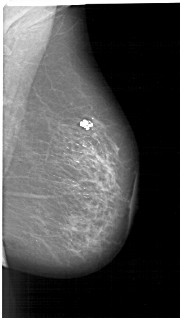

A_1276_1.RIGHT_MLO

RIGHT_MLO LINES 5716 PIXELS_PER_LINE 3226 BITS_PER_PIXEL 12 RESOLUTION 43.5 NON_OVERLAY